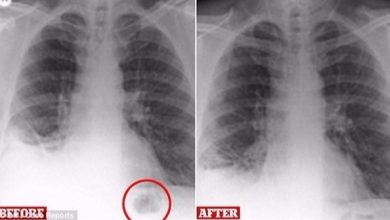

طريقة بسيطة لتنظيف الرئتين من ” النيكوتين “

هذه الأطعمة و المشروبات تنظف الرئة من الغبار و السموم